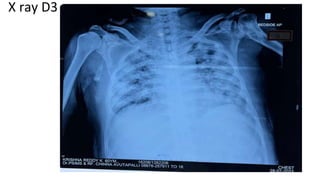

X ray D3

• Pulmonology review was done i/v/o

CHEST x ray shows- Bilateral non- homogeneous opacities- ? Bilateral

Consolidation